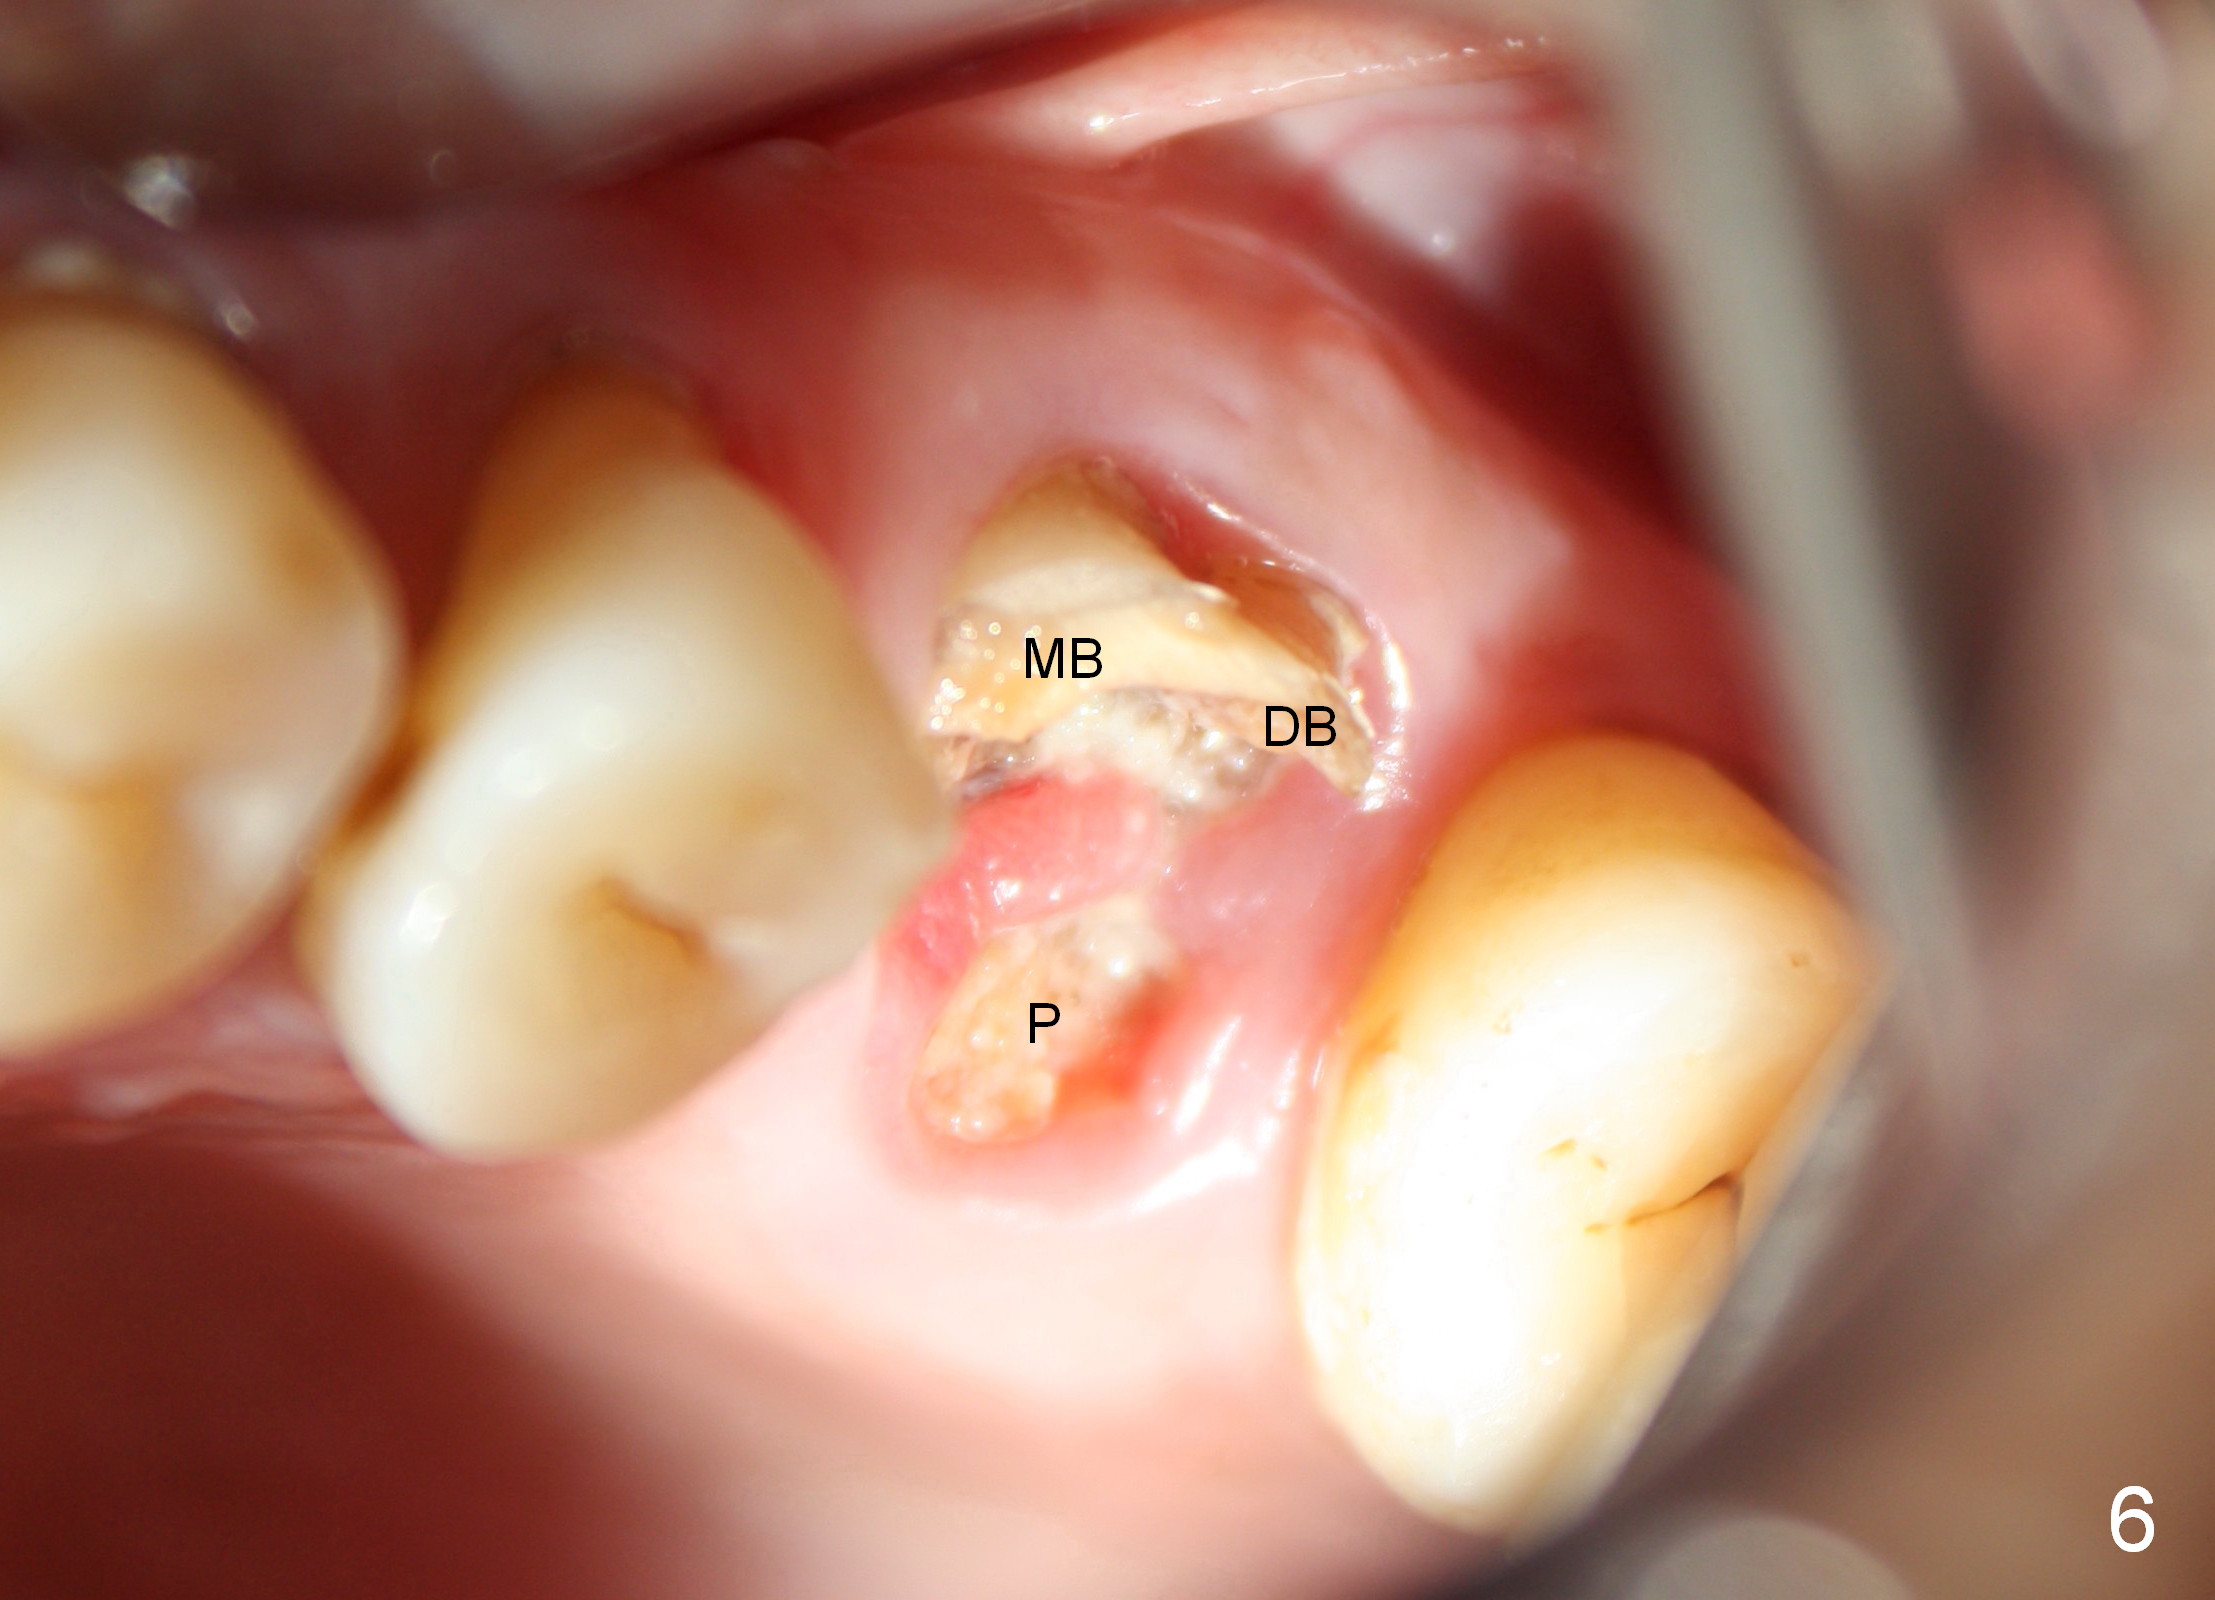

A 49-year-old man requests to restore #14 with residual roots (Fig.1). There is periapical radiolucency (Fig.2 *). A 5.9x10 mm bone-level implant is placed with minor sinus lift (Fig.3), whereas a short (Fig.4) or long (Fig.5) tissue-level implant is placed without or with sinus lift. The implant could be as large as 7 mm (Fig.5) to prevent post-extraction ridge atrophy.

It appears that the palatal root (Fig.6 P) is separated from the buccal ones (MB, DB). Connection between the latter appears to be weak (Fig.2) and could be broken using proximators or small straight elevator.